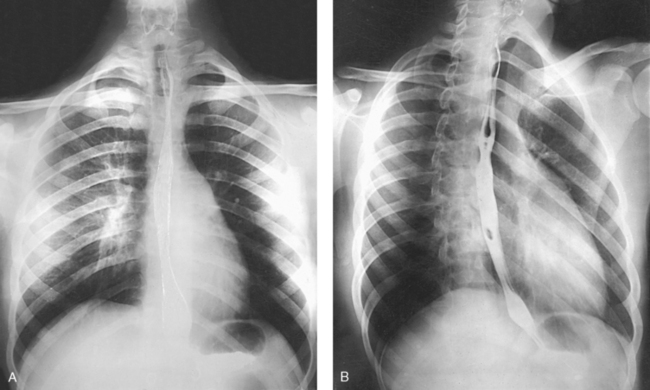

For radiography of the heart and lungs, the patient is placed in an upright position whenever possible to prevent engorgement of the pulmonary vessels and to allow gravity to depress the diaphragm. Of equal importance, the upright position shows air and fluid levels. In the recumbent position, gravitational force causes the abdominal viscera and diaphragm to move superiorly; it compresses the thoracic viscera, which prevents full expansion of the lungs. Although the difference in diaphragm movement is not great in hyposthenic individuals, it is marked in hypersthenic individuals. Figs. 10-10 and 10-11 illustrate the effect of body position in the same patient. The left lateral chest position (Fig. 10-12) is most commonly employed because it places the heart closer to the IR, resulting in a less magnified heart image. Left and right lateral chest images are compared in Figs. 10-12 and 10-13.

When pneumothorax (gas or air in the pleural cavity) is suspected, one exposure is often made at the end of full inspiration and another at the end of full expiration to show small amounts of free air in the pleural cavity that might be obscured on the inspiration exposure (Figs. 10-16 and 10-17). Inspiration and expiration radiographs are also used to show the movement of the diaphragm, the occasional presence of a foreign body, and atelectasis (absence of air).

For certain conditions, such as pneumothorax and the presence of a foreign body, radiographs are sometimes made at the end of full inspiration and expiration (Figs. 10-29 to 10-31). Pneumothorax is shown more clearly on expiration because collapse of the lung is accentuated.